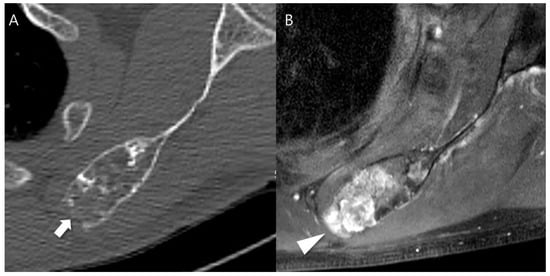

First, radiodensity measurements were performed using a picture archiving and communication system (PACS) workstation (Zetta PACS, TaeYoung Soft, Anyang-si, Republic of Korea). The independent evaluation of images was performed by two musculoskeletal radiologists. Both readers were blinded regarding clinical information including surgery and histopathological results. A region of interest (ROI) marker was placed around the lesion with the use of the freehand ROI tool, which produced the maximum, minimum, mean, and standard deviation (SD) values of the lesions’ radiodensity in Hounsfield units (HU; HUmax, HUmin, HUmean, and HUSD). The CT slice on which the lesion had the largest cross-sectional area was selected. Among these, the axial slice with an abundant mineralized matrix and increased radionuclide uptake as seen on fused SPECT/CT images were selected. The freehand ROI was drawn to contain the lesion only within the intramedullary canal, ensuring that the bony cortex was not included within the ROI. When the lesion margin was not well visualized, the fused SPECT/CT image or MRI were referenced (Figure 1).

Any aggressive CT features for the grading of central cartilaginous bone tumors including (i) deep endosteal scalloping ≥ 2/3 of the normal cortical thickness (Figure 1), (ii) extensive endosteal scalloping ≥ 2/3 of the lesion length (Figure 2), (iii) expansile cortical remodeling (Figure 3), and (iv) cortical destruction with or without soft tissue extension (Figure 4) were also evaluated. The CT images were evaluated in conjunction with the plain radiographs and/or MRI. After finishing the independent review, a consensus review of the CT was performed. The two radiologists reviewed the CT images together to reach a final consensus on discrepant interpretations from the independent reading.

Figure 1. Radiodensity measurement in a patient with ACT in the distal femur. (A) Axial CT image shows a lobulated mass containing chondroid matrix mineralization and focal deep endosteal scalloping ≥ 2/3 of the normal cortical thickness (arrow). (B) Mean (±SD) attenuation of this lesion was measured using the freehand ROI tool (green line) and HU values were found to be 435.49 ± 335.30 [−111 to 1501]. (C) Fused SPECT/CT image shows the radioactive uptake with SUVmax of this lesion which was calculated to be 23.71.